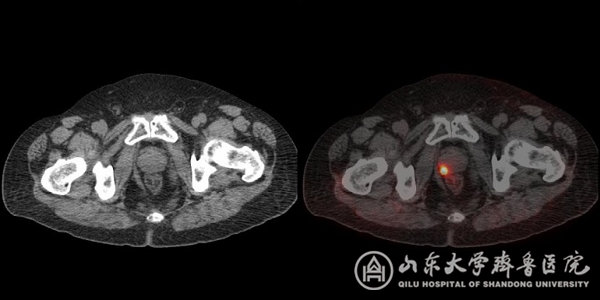

图1 PSMA显像清晰显示前列腺癌原发灶

图2 直径只有4毫米的转移淋巴结